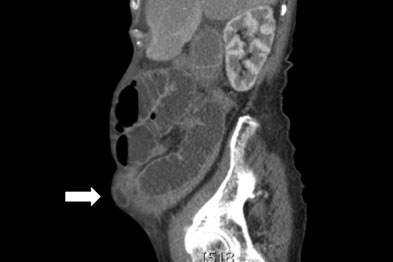

The protrusion of organs in the abdominal cavity is a common sign of hernias. For the precise diagnosis and treatment, and abdominal CT scan can be helpful to reduce the risk of complications during or after the surgery. The overlapping of symptoms with gastrointestinal diseases makes it a difficult diagnosis.

The clinical manifestations are often inconclusive and peri-operative assessment is recommended in most cases. The grade of obstruction is identified with the imaging techniques used. Moreover, the compromised blood supply can lead to ischemia. The afferent bowel loops are affected in this case.